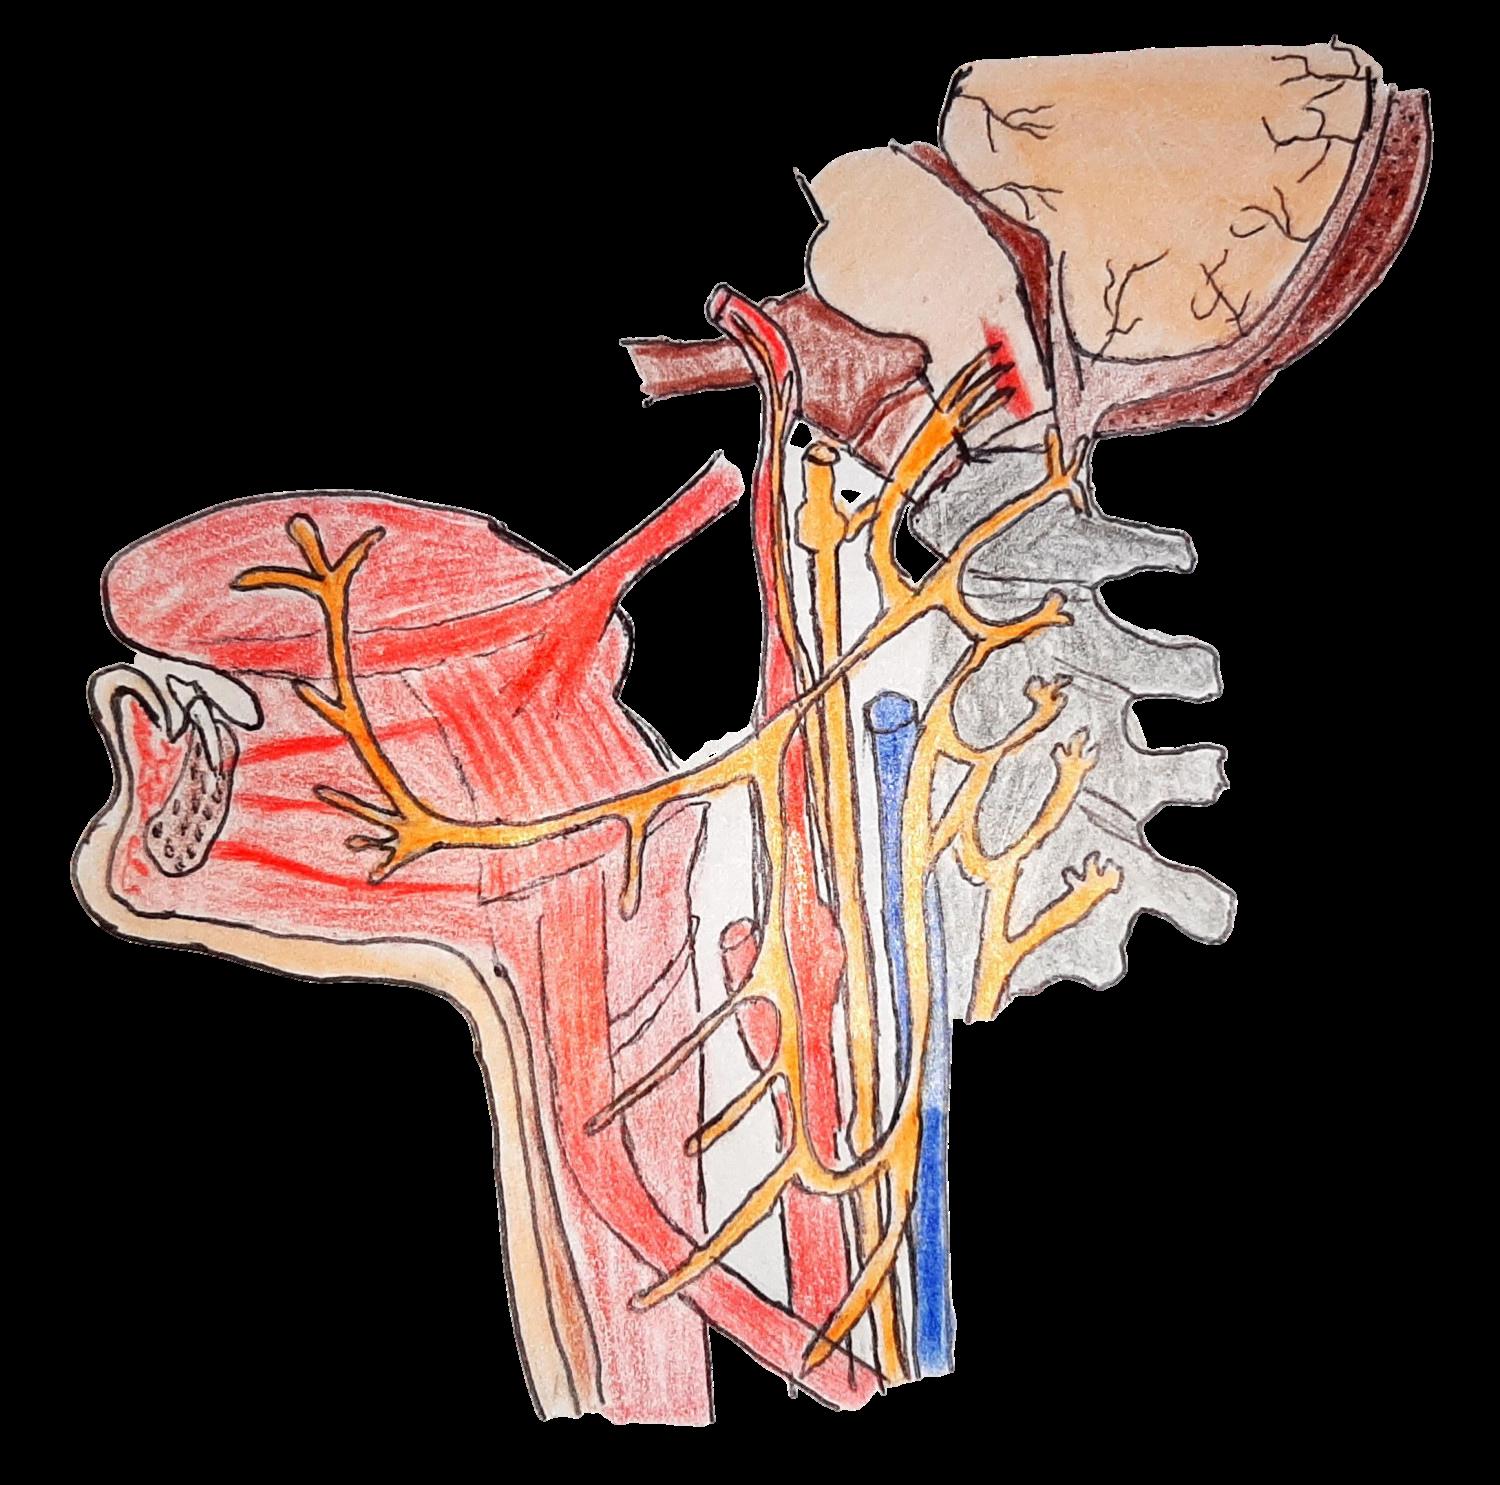

NERVIO GLOSOFARÍNGEO (IX PAR)

Glándula salival parótida

CARACTERÍSTICAS:

Médula oblongada NERVIO GLOSOFARÍNGE O

Es un nervio mixto, tiene una función motora y sensorial Es el nervio del reflejo nauseoso y la deglución Encargado de modular los tiempos de la deglución, función compartida con los nervios facial y vago

Ramas linguales

Arteria carótida común